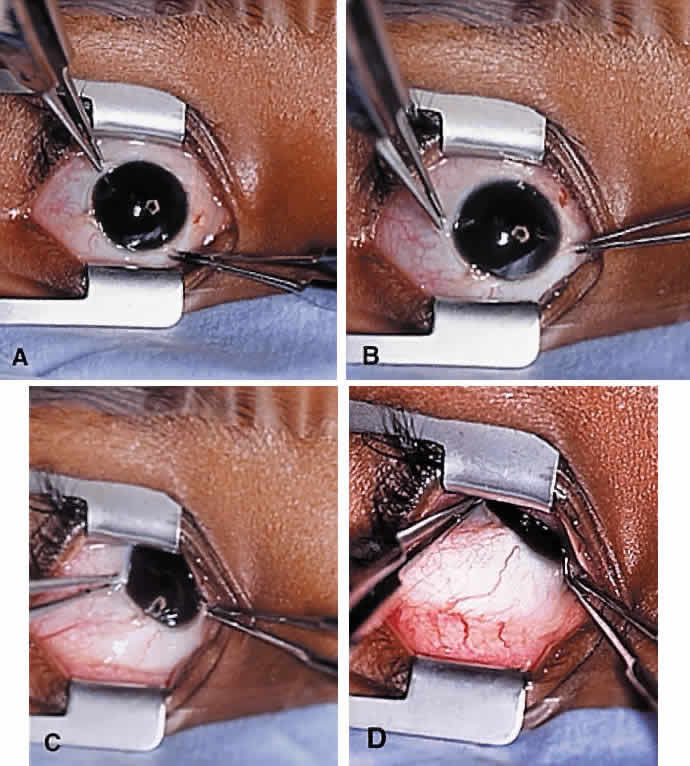

To perform the procedure, either general anesthesia or local anesthesia with intravenous sedation may be selected. Following anesthesia, it is often helpful to assess tendon laxity by performing an exaggerated traction test.47 A normal superior oblique tendon can be differentiated from a lax tendon when the globe is rotated upward, inward, and retropulsed into the orbit (Fig. 3).23

The superior oblique tendon tuck is best performed near the tendon's insertion as described by McLean.48 The surgical procedure is performed through a superior temporal cul-de-sac approach (Fig. 4). With the globe depressed, an incision is made through the conjunctiva and Tenon's fascia just temporal to the lateral border of the superior rectus muscle and parallel to the corneoscleral limbus. The superior rectus muscle is engaged on a muscle hook and the globe adducted and positioned in maximal depression. The lateral rectus muscle may also be used to assist positioning the globe. Using two small muscle hooks, the conjunctival incision is stretched open posteriorly in a triangular fashion. The lateral border of the superior rectus muscle is elevated and displaced medially. The globe is then examined for the glistening, white fibers of the superior oblique tendon running flush against the sclera and directed anteromedially. The anterior portion of the reflected tendon typically inserts under the lateral border of the superior rectus muscle, 5 to 7 mm posterior to its insertion. However, this location may vary, and anatomic anomalies are common (Fig. 5).12,37,47,48 The superior oblique tendon looks very different near its scleral insertion than 10 mm more proximally, where it becomes cordlike and enters Tenon's fascia after passing under the belly of the superior rectus muscle. Inexperienced surgeons have mistaken the lateral portion of the tendinous insertion of the superior rectus muscle for the superior oblique tendon (Fig. 6).49 However, the superior rectus muscle travels toward the orbital apex and contains prominent anterior ciliary blood vessels, whereas the superior oblique tendon is directed toward the trochlea and is usually avascular. In addition, direct traction on the superior oblique tendon can easily be palpated at the trochlea by pressing a finger over the eyelid in the superior nasal quadrant of the orbit.10 This is a reliable sign that the tendon (and not some other structure) has been engaged on the muscle hook.